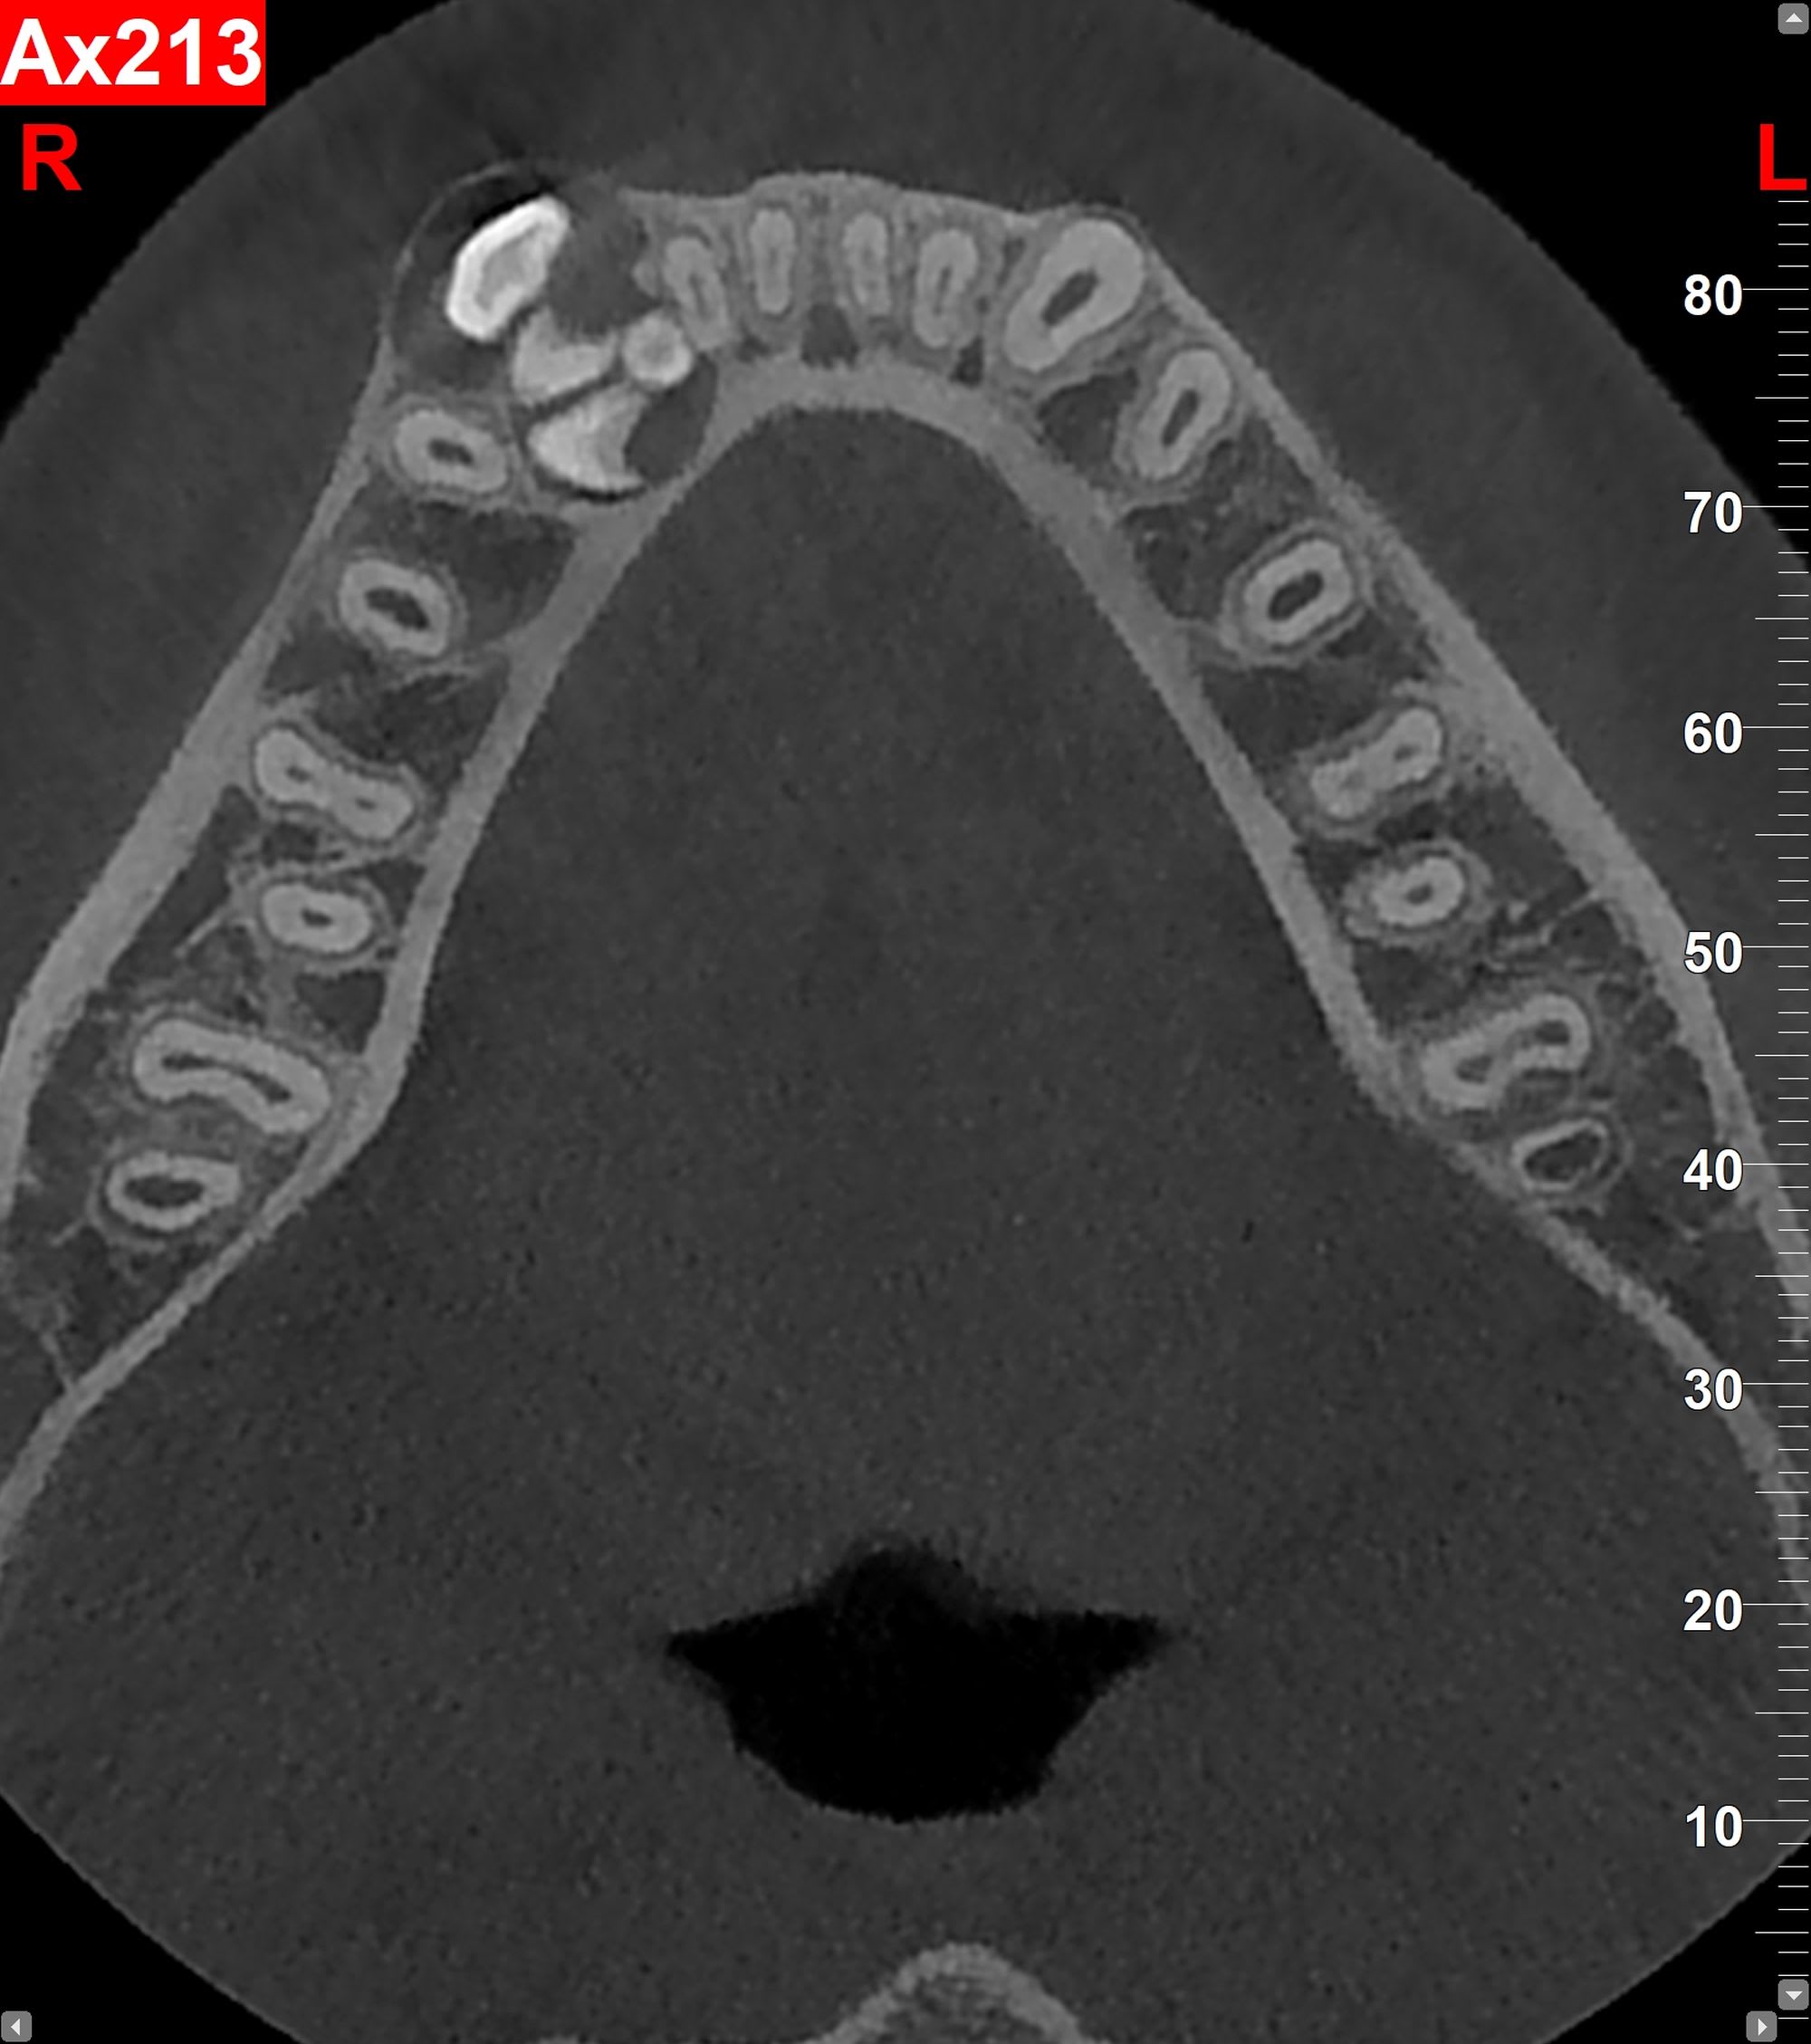

Je suis allé à la pêche aujourd’hui chez un enfant de 12 ans.

J'en ai sorti 8.

A votre avis comment ça cicatrise après?

Est ce que tracter la 43 en lingual risque d'être dangereux au niveau paro?

Y'a une explication à la présence d'autant d'odontoïdes alors que la 43 semble normale ?